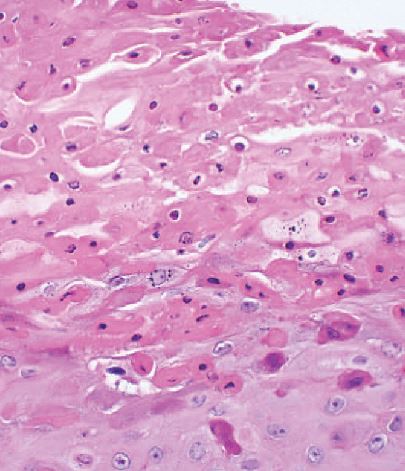

In addition to clinical diagnosis, HBID can also be diagnosed histopathologically. Ocular and oral plaques are distinctively characterized by acanthosis, dyskeratosis, and parakeratosis within the stratified squamous epithelium. The hallmark dyskeratotic cells in hereditary benign intraepithelial dyskeratosis have a dense cytoplasm and pyknotic nuclei. Beneath the epithelium in the stroma lies a chronic, mid to moderate lymphocytic inflammatory response. The adjacent stratified squamous epithelium of the conjunctiva can be normal or acanthotic[14][3].

In 1977, Sadeghi and Witkop performed an ultrastructure study using electron microscopy to compare HBID with other disorders of the oral mucosa. They observed that cells in affected HBID patients had a shift in differentiation toward keratinization. Additionally, cells contained densely packed tonofilaments in the cytoplasm, numerous vesicular structures, and disappearance of cellular desmosomes and interdigitations[16].